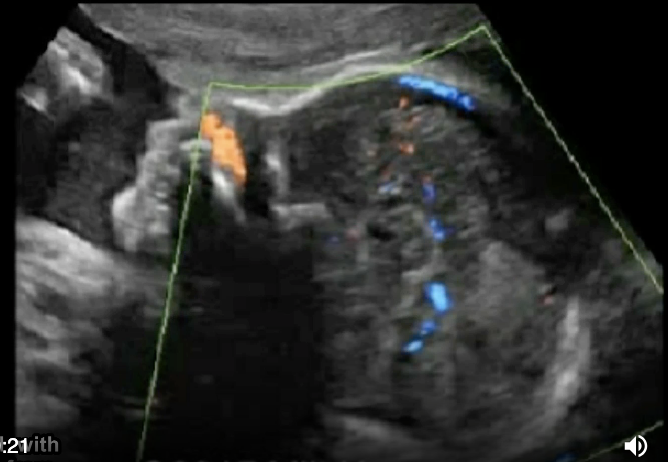

the color doppler portion shows

a) no pericallosal artery

b) thrombus of vein of galen

c) normal fetal anatomy

d) no circle of willis